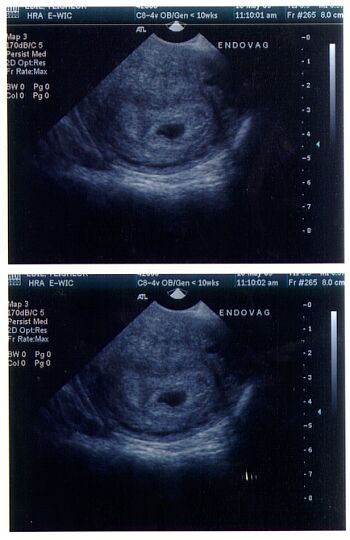

5 1/2 week ultrasound of gestational sac